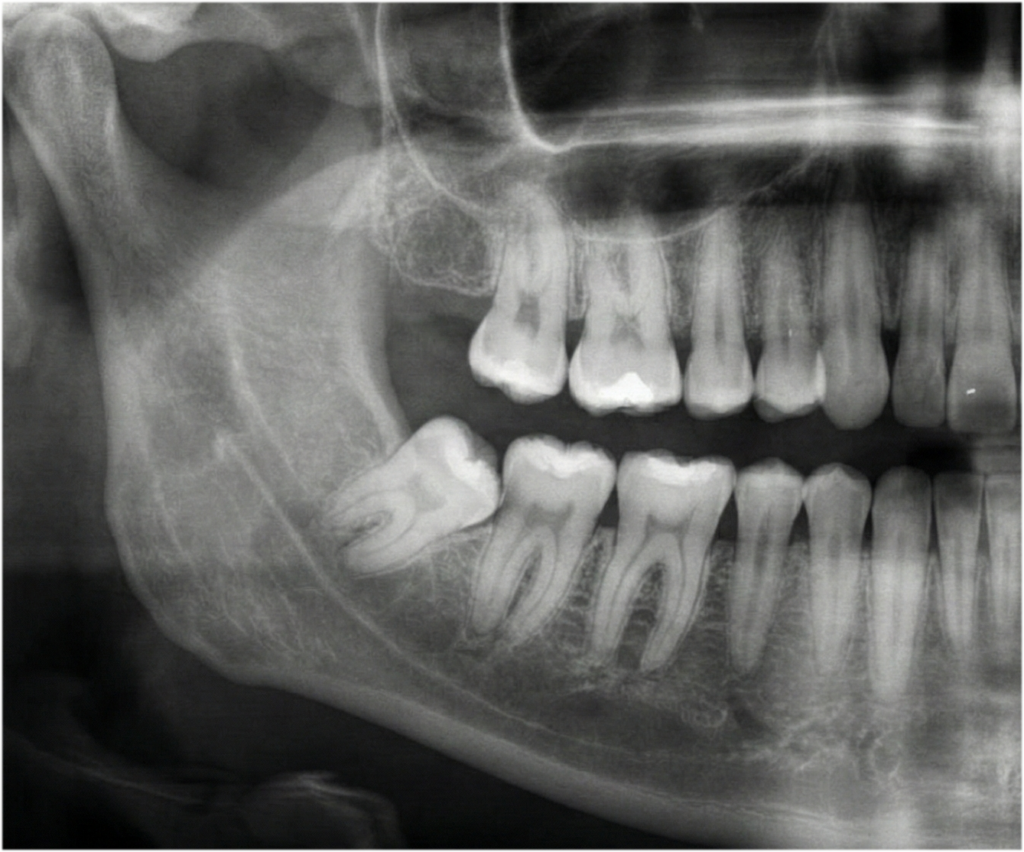

단순 발치부터 대학병원 전원이 필요한 완전 매복 사랑니까지. 풍부한 임상 데이터를 보유한 원장이 직접 진단하고 시술합니다. 어려운 사랑니일수록 경험이 중요합니다.

정밀 진단과 안전 최우선

최첨단 CT를 통해 사랑니의 뿌리 형태, 하치조 신경과의 거리를 0.1mm 단위까지 정밀 분석합니다. 정확한 진단이 안전한 시술의 첫걸음입니다.